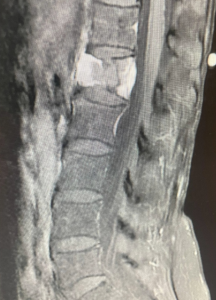

She presented with back pain and Leiomyosarcoma which had spread to the L1 vertebral body. Radiation treatments and cement injection to L1 were tried by the oncologists but her vertebrae collapsed anyway. The first 2 MRI pictures show the progressive collapse.

She was taken to surgery about 4 1/2 years ago and the entire L1 vertebrae and tumor was surgically removed from the front and back with the help of a vascular surgeon. I had to place extensive hardware from the front and back to support the missing vertebrae. She recovered well. Recent CT scans showed no further cancer in the spine. (Photos 3-5.)